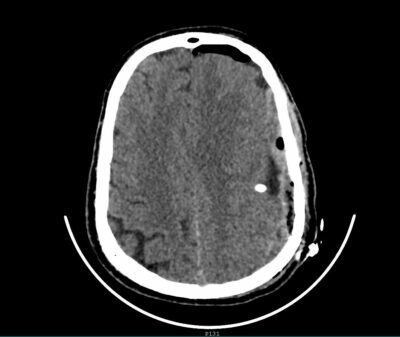

وأوضح رئيس القسم الدكتور زهير هوساوي الذي أجري العملية أن المريض قد قدم لقسم الطوارى وهو يعاني من صداع شديد وفقدان النطق وضعف الحركة بالجانب الايمن من عدة شهور وبعد الفحص السريري والأشعة اتضح وجود اكياس نزفيه بجانب منطقة الحركة والكلام في الدماغ مما استلزم إجراء العملية باستخدام المايكروسكوب والمنظار التي تُعد من أحدث التقنيات العلاجية في هذا المجال وتم ازالة التكيسات في المناطق الدماغية كاملة مع المحافظه على منطقة الحركة والكلام بفضل الله ثم التطور الهائل في مجال الخدمات الطبية والعلاجية الذي تواكبه قطاعاتنا الصحية بدعم واهتمام كبير من القيادة الرشيدة -رعاها الله – وحرصها على توفير أفضل و أحدث الإمكانيات المتطورة تم اجراء العملية بنجاح تام وعودة النطق والحركة لطبيعته السابقة لدى المريض .